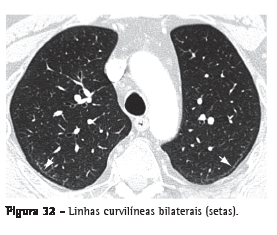

Linha curvilínea subpleuralOpacidade curvilínea de 1-3 mm de espessura, de localização subpleural, com distribuição paralela a sua superfície (Figura 32). É um indicador não específico de atelectasia, edema, fibrose ou inflamação.(3,7)